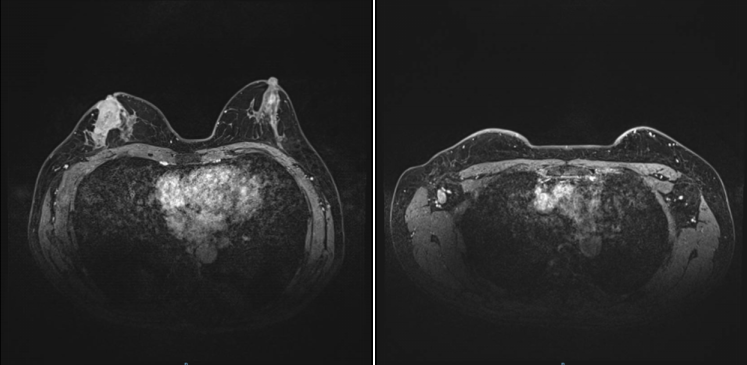

2021-11-30,钼靶:右乳外上象限较高密度肿块影,有浅分叶,约1.4×1.3cm大小,其内及邻近簇状分布细小多形钙化,符合乳腺癌诊断,BI-RADS 6类。右腋下见增大淋巴结影,约1.8cm直径大小。(图1)

图1.钼靶(2021-11-30)